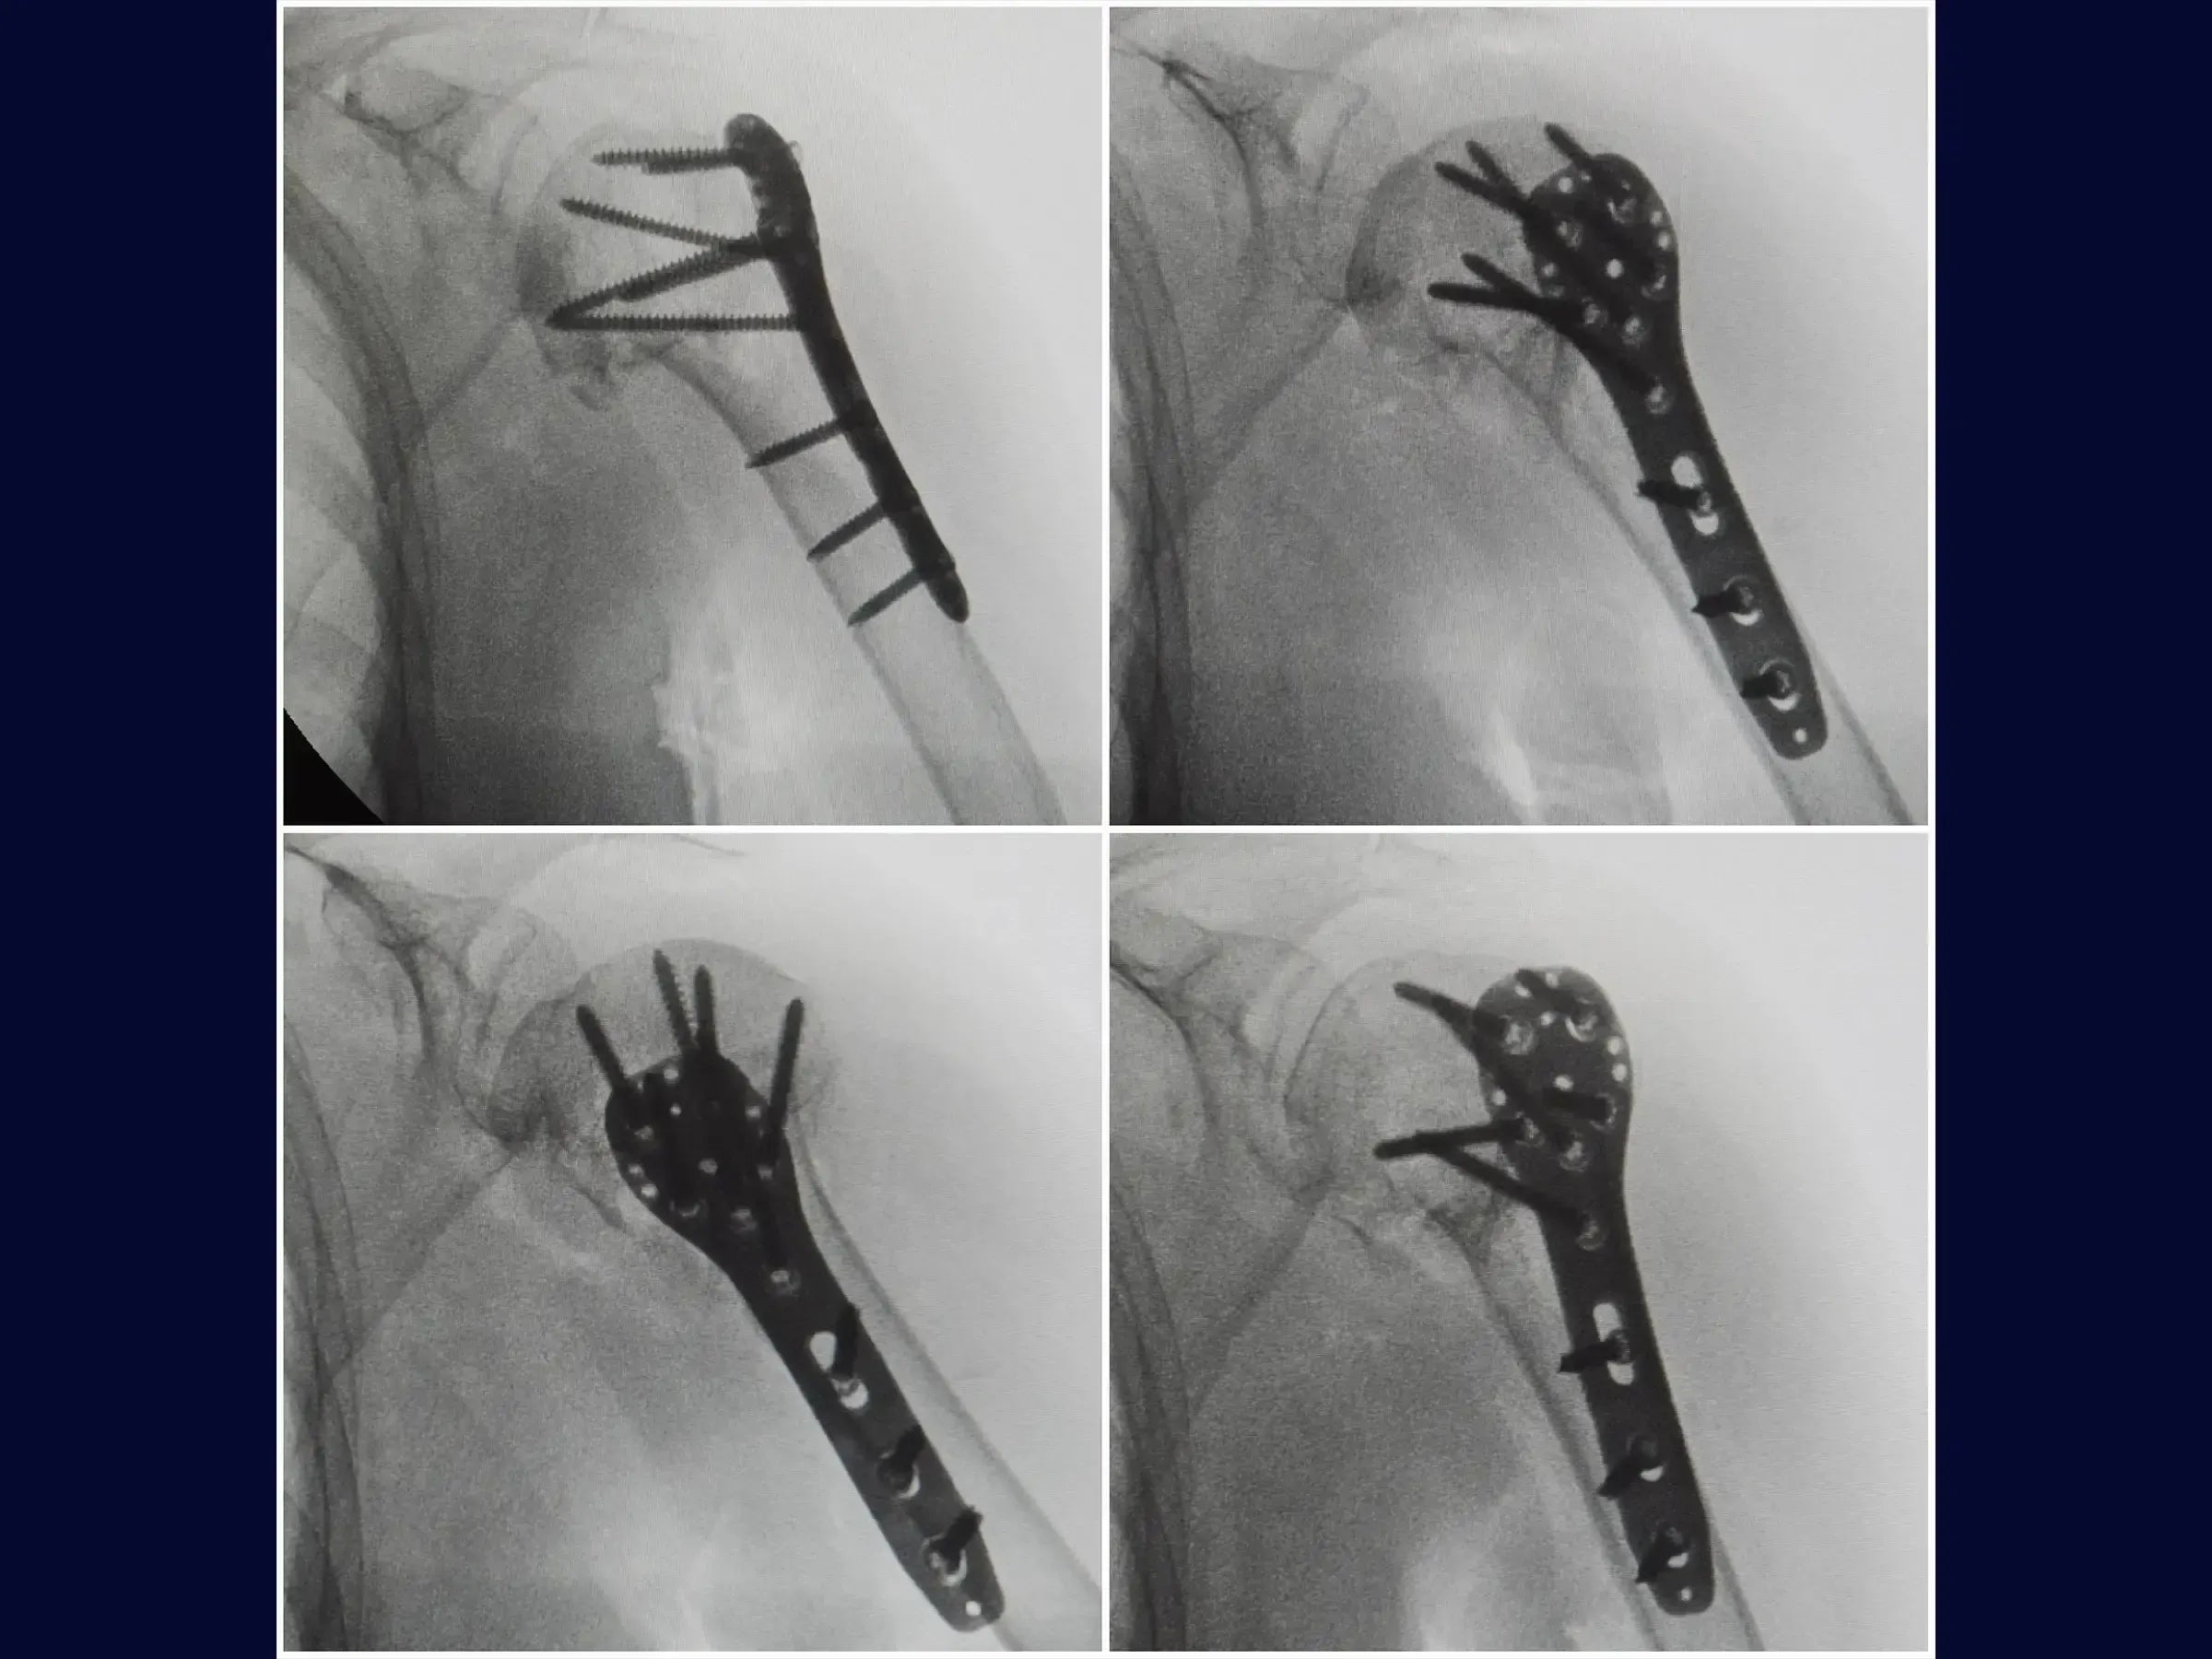

- Fixação com placa e posicionamento de parafusos.

- Fixação Provisória Efetiva: Utilização de fio de Kirschner para estabilização provisória fora da área de implantação da placa.

- Técnica de Plaqueamento Otimizada: Protocolos para posicionamento da placa e inserção sequencial de parafusos, incluindo o parafuso do calcar como guia fundamental para o alinhamento.

- Perfuração Segura: Metodologia de perfuração com broca de alta rotação e pouca força para evitar transfixação da cartilagem articular.

- Avaliação Intraoperatória Detalhada: Análise radiográfica para verificação da altura da placa, redução da fratura e centralização da placa, assegurando a distribuição adequada dos parafusos.